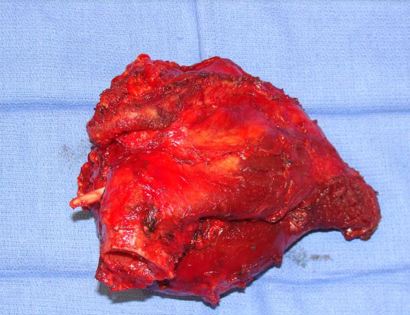

This is an image of the specimen with the tumor removed in its entirety.